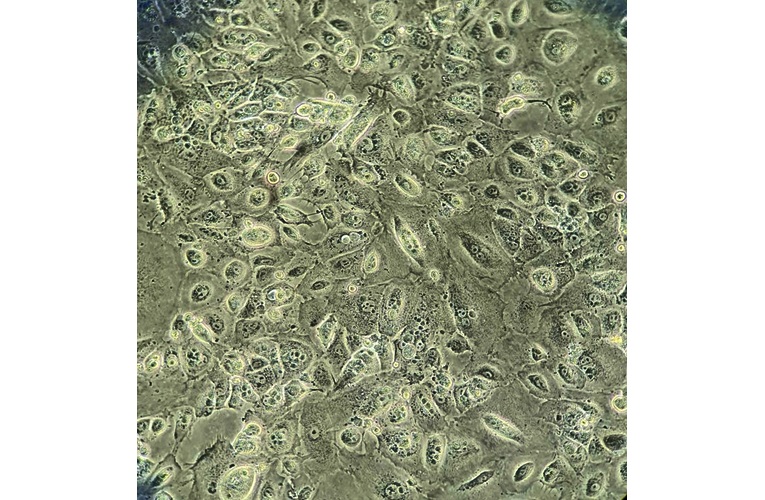

- Morphology: Polymorphic trapezoid cells arrenging in a cobblestone appearance with large cytoplasmic surface area

- Description: The cell line established directly from a tumor compartment (ascites) of chemonaive HGSOC patient. Thus it closely recapitulates the tumor compartment as it emerged in these patients.